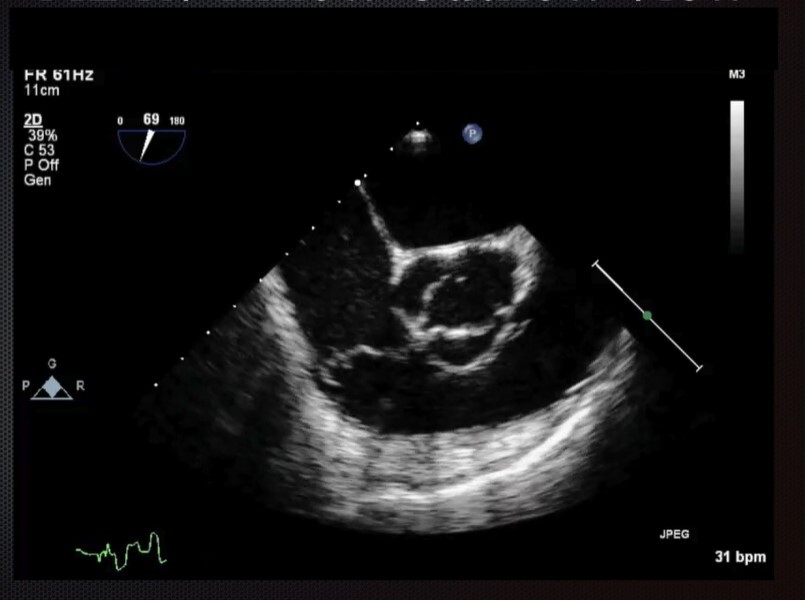

Mid-Esophageal 4 chamber view. Structures: R atrium, R ventricle, L atrium, L ventricle, anterior and posterior mitral leaflets. 30-35 cm into the esophagus. Turn R until you center on mitral valve. Plane to 10-20 degrees.

Mid-Esophageal 2 chamber view. Multiplane to between 80-100 degrees.